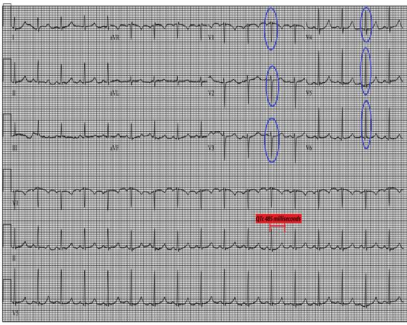

(1) 下肢B超:检查结果排除深静脉血栓形成(2)心电图:显示为窦性心律,存在 R 波递增不良(QTc 485ms)(图1),可排除急性冠脉综合征;(3)胸部 X 线(入院时):可见双侧斑片状阴影及双侧胸腔积液(图2);(4)病原学检查:入院时血培养、尿培养结果均为阴性,且住院期间无感染相关症状与体征,因此双侧斑片状阴影由感染因素导致的可能性较低,更倾向于与急性心力衰竭相关;(5)肺血管 CTA:因患者存在心悸、呼吸急促症状且 D - 二聚体水平轻度升高,遂完善此项检查以排除肺栓塞。结果显示双侧中量胸腔积液、轻度间质性肺水肿及轻度心脏肥大,提示存在充血性心力衰竭(CHF)(图 3、图 4),同时可见散在肺部阴影;(6)经胸超声心动图(TTE):显示左右心室大小正常、收缩功能正常,无局部壁运动异常;左心房大小为 2.93cm(正常范围 1.9-4.0cm),处于正常水平;肺动脉收缩压(PASP)为 34mmHg,存在轻度同心性左心室肥大,心室射血分数为 55%-60%。 (7)核素心肌灌注显像负荷试验:因心电图异常进行此项检查,未发现可逆性缺损,表明无心肌缺血;(8)腹部 / 盆腔 CT:患者肝炎免疫检测结果为阴性,肝转氨酶升高大概率由充血性心力衰竭(CHF)继发的充血性肝淤血引起。为进一步明确情况,行腹部 / 盆腔 CT 检查,显示存在胆结石、胆囊壁增厚 / 水肿、门静脉周围水肿所致的轻度肝肿大,同时伴有新出现的轻度全身性水肿及少量盆腔积液;(9)胸部 X 线(出院时):显示肺充血消退,双侧胸腔积液较入院时减少(图 5)。

图1